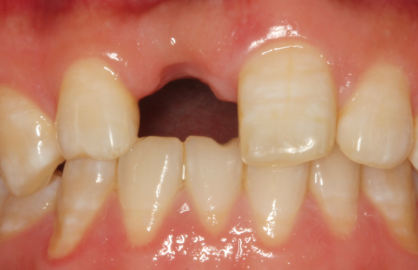

一、可摘局部义齿:经济实用的“可拆卸方案”

什么是活动假牙?

它是一种利用金属卡环(俗称“挂钩”)抱紧邻牙,同时依靠基托覆盖在牙龈和牙槽骨上来获得固位与支撑的修复体。患者可以自行摘戴。

图1.活动义齿

它的核心特点:

优点:

1. 适应症广泛: 几乎适用于各种牙齿缺失情况,无论是单颗、多颗还是末端游离缺失(最后面没有牙)。

2.  价格亲民: 是三种方案中费用最低的一种。

3.  制作快捷: 通常一到两周即可完成,治疗周期短。

4.  微创无痛: 无需手术,仅需取模和少量备牙,对全身健康状况要求低,非常适合年老体弱或有手术禁忌症的患者。

缺点:

1.  异物感强: 较大的基托和金属部件会占据口腔空间,初戴时可能影响发音,并产生明显的异物感。

2.  咀嚼效率较低: 其稳定性不如固定假牙,恢复的咀嚼功能也不如天然牙

3.  不便之处: 每次饭后需取下清洗,睡前还需浸泡,日常护理相对繁琐。

4.  可能损伤邻牙: 金属卡环长期摘戴可能对作为“基牙”的健康牙齿造成一定磨损。

最适合人群: 预算有限、全身情况较差无法耐受手术、或缺失牙较多且作为过渡性修复的患者。